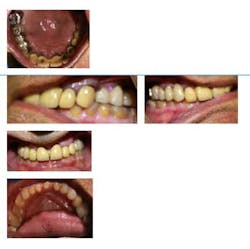

Fig. 3: Intraoral preoperative photographs

The patient has ground through the porcelain on the lingual surfaces of the crowns on Nos. 6, 7, and 9.

The occlusal surfaces of the posterior teeth and incisal edges of the anterior teeth in the mandibular arch have considerable wear due to the fact that the patient is a bruxer. He is grinding natural tooth structure in the mandible against porcelain in the maxilla. Enamel is softer than porcelain and wears away quicker when the patient functions and grinds his teeth.